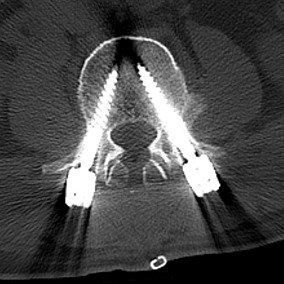

陈勇主任在医学3D打印技术团队的支持下,通过术前采集患者目标椎体的三维信息,运用3D打印技术重建脊柱三维模型,设计椎弓根螺钉的置入钉道,有效控制置钉的位置、方向及角度,从而提高置钉的准确性和成功率,以减少术中置钉过程中神经损伤的风险。

▲3D打印直观显示椎体结构,指导手术精准置钉

▲术中椎弓根螺钉精准置入

▲术后复查X线、CT